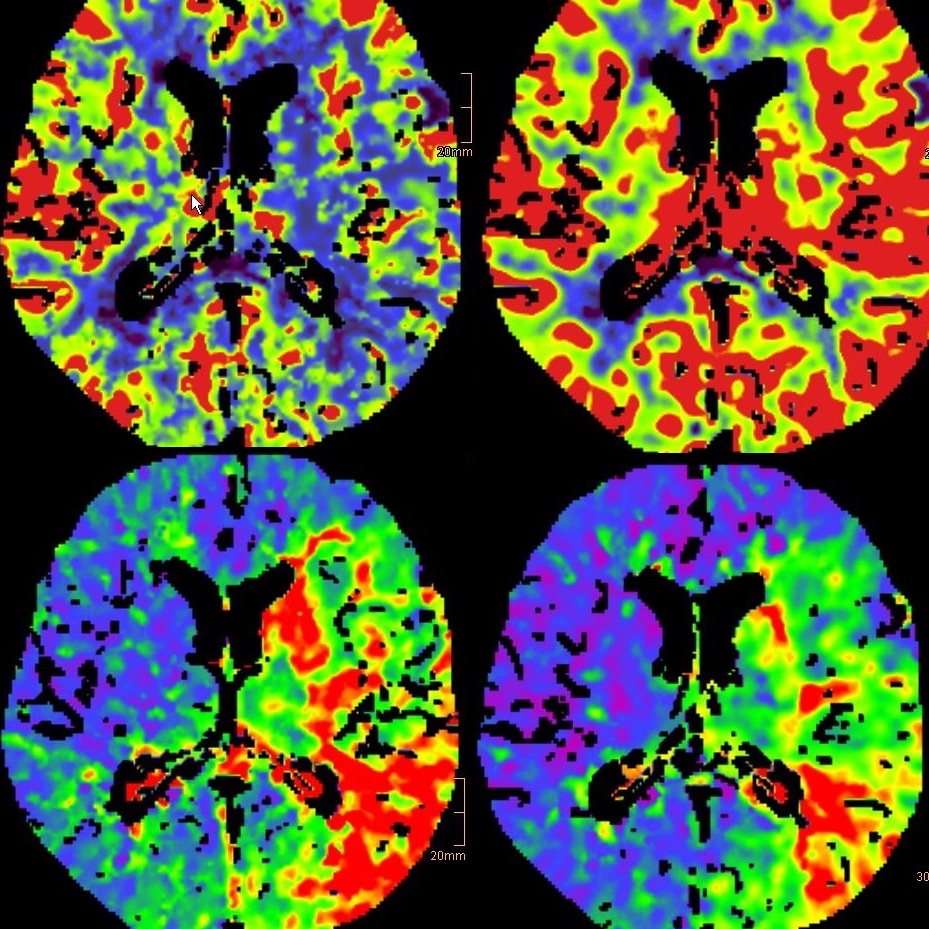

Hierfür werden neuroradiologische Arbeitsplätze direkt im CT und im MRT vorgehalten. Die Auswahl der Untersuchungstechnik und die Befundung wird von unseren NeuroradiologInnen mit spezieller Expertise in den modernsten Techniken individuell auf den Patienten zugeschnitten.

Wir verfügen über drei CTs inkl. einem Dual energy CT der neuesten Generation, sowie 3 MRTs, davon ein 3 Tesla Gerät, mit dem sich besonders hochauflösende Bilder erstellen lassen.